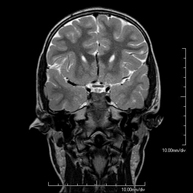

- RM Cerebral (cranial)

Prova diagnòstica no invasiva que consisteix en l'obtenció d'imatges d'alta definició anatòmica del cerbell mitjançant l'ús d'un camp electromagnètic i ones de ràdio (com un emissor i un receptor). No utilitza radiació ionitzant. Indicacions: problemes vasculars, pèrdua de memòria, epilèpsia, cefalea, malformacions, sospita de tumor, meningitis. - RM de Cais